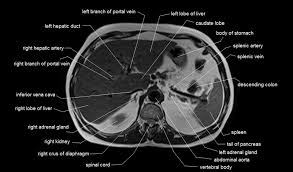

This MRI abdomen axial cross sectional anatomy tool is absolutely free to use. This section of the website will explain large and minute details of abdomen axial  ...